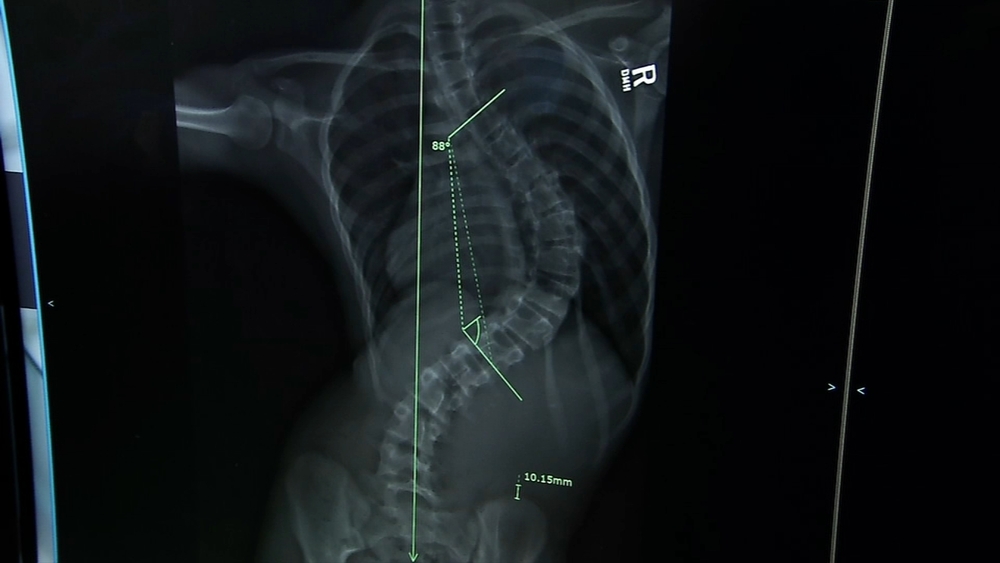

Cindia has been dancing since pre-school. When she was nine, doctors noticed a curvature in her spine. She was diagnosed with scoliosis.

She wore a brace for four years and continued to dance, but while on vacation her mother noticed the curve had gotten significantly worse. Her doctor said she'd need surgery.

Typically, spinal fusion is performed, which is where metal rods are inserted to reposition the spine. But Dr. Ryan Goodwin at Cleveland Clinic Children's Hospital suggested a more flexible solution.

"Tethering is an option for patients who still have growth remaining and their curves are large enough. Imagine their spine is curved like this. We apply the tether to this side, so what that would do is it straightens a little bit and keeps this side from growing and as the child begins growing, this side will continue to grow over time, depending on how much growth they have remaining," he explained.